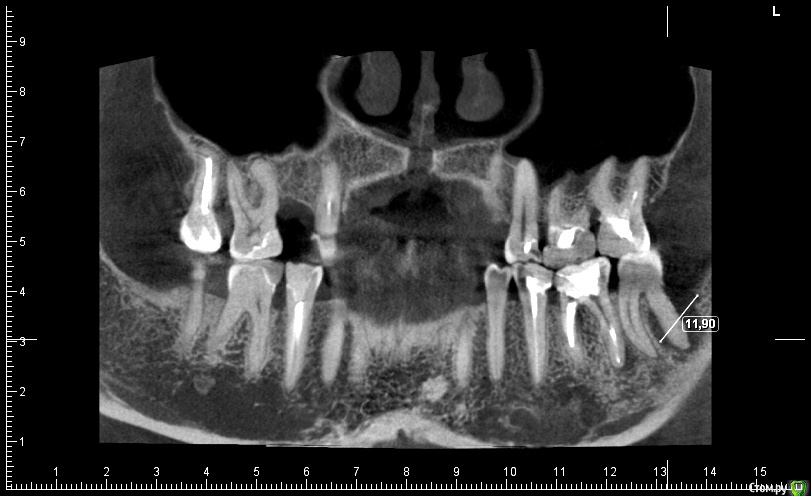

ceti Опубликовано 18 декабря, 2015 Поделиться Опубликовано 18 декабря, 2015 Здравствуйте! Зуб 37 с недавнего времени стал безпокоить, ощущается дискомфорт, тянущие ощущения в районе скулы. На осмотре доктор обнаружил паталогический карман через который отделяется гной или серозная жидкость. Сделали КТ: Полностью, вся томограмма: https://drive.google.com/open?id=0BwAD98i97KuPbUpFdGcxeXRNMjg Предыдущий КТ (февраль этого года): https://drive.google.com/open?id=0BwAD98i97KuPflhOam1lTzJsTkhBNFNVdUFmb3lHWWJ3Rll2Z1BTVDUteURyNTNUdElSems Насколько я понимаю, в феврале проблемы не было вообще, либо она была незначительна. Зуб несколько раз травмировался -- во время еды попадал твердый предмет, достаточно неприятное чувство. Вероятно, вследствие этого на жевательной поверхности появился скол пломбы, место скола чувствительно к прикосновению зондом. Также (возможно это важно) намного ранее было сильное воспаление связанное с соседним 8-ым зубом. Тоже был обширный карман, эту 8-ку удалили лет пятнадцать назад. Еще, полгода назад было проведено перелечивание каналов соседнего 36 зуба. Посоветуйте пожалуйста стоит ли пытаться лечить этот зуб или лучше его удалить. На консультации мне предложили такую последовательность действий: 1) Эндодонтия под микроскопом2) Кюретаж (вероятно открытый)3) Остеопластика4) Плазмалифтинг Есть ли смысл пробовать и насколько велики шансы на успех? Если зуб нужно удалять, то насколько срочно. Еще, соседний зуб 36 имеет воспаление у верхушки корня соседнего с 37, есть ли риск его задеть при удалении 37-го зуба? Заранее благодарю за ответ. Ссылка на комментарий

ceti Опубликовано 21 декабря, 2015 Автор Поделиться Опубликовано 21 декабря, 2015 Здравствуйте! По результатам очного осмотра доктор исключил трещину и предположил парадонтальную проблему. Есть какое-то объяснение, что могло послужить причиной и почему процесс так быстро прогрессировал? Ниже фрагмент КТ, который был сделан в феврале этого года и свежий снимок: Заранее благодарю. Ссылка на комментарий